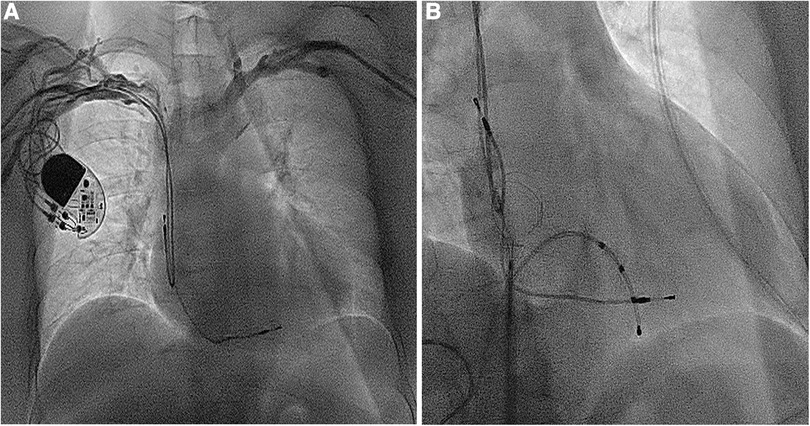

Figure 1

(A) The dual-chamber pacemaker implanted for III degree atrioventricular block 14 years ago; (B) the atrial and ventricular leads removed using a needle's eye snare through the inferior vena cava.

A 59-year-old woman was admitted due to pacemaker pocket infection. A dual-chamber pacemaker was implanted 14 years ago due to III degree atrioventricular block. No history of infiltrative cardiomyopathy, myocarditis, or coronary artery disease. There was also no history of cardiac surgery or connective tissue disease. The pacemaker pocket infection lasted for two months and was unresponsive to antibiotic therapy. There were no vegetations on the leads. Additionally, the blood cultures were negative. Indications for lead extraction were confirmed, and the patient informed consent was obtained. The atrial and ventricular leads were removed through the right femoral vein using a needle's eye snare (Figure 1). Hypoxemia (FiO2 61%/PaO2 64.3 mmHg) was observed immediately after the removal of the lead. Pericardial effusion was ruled out by x-ray fluoroscopy, and the pulmonary arteriogram did not show any filling defects in the main pulmonary arteries. The computed tomography pulmonary angiogram (CTPA) did not show any signs of pulmonary embolism, and the chest CT did not reveal any significant lesions. As peripheral pulmonary embolism could not be ruled out completely, anticoagulation therapy was initiated. Neither oxygen therapy with a mask (oxygen flow rate of 7.7 L/min) nor noninvasive mechanical ventilation (BiPAP: IPAP = 11 cmH2O, EPAP = 5 cmH2O, FiO2 = 100%) was effective in relieving hypoxemia. Pulse oxygen saturation (SpO2) was measured in both supine and upright positions. The results showed 89% in the supine position and 77% in the upright position (Figure 2). Therefore, we considered the diagnosis of Platypnea-Orthodeoxia. A PFO with intracardiac shunt was suspected. Transesophageal echocardiography revealed a PFO (see Supplementary material: Video 1 and 2), and right heart contrast echocardiography showed the presence of a right-to-left intracardiac shunt, without any signs of pulmonary hypertension or elevated pressure in the right heart (Figure 3). As the patient was pacemaker-dependent, a dual-chamber permanent pacemaker was re-implanted. After re-implantation, the patient's SPO2 levels were monitored at 82%–89% without oxygen inhalation. Although the patient was hypoxemic, her hemodynamic and metabolic parameters were normal. After 10 months of follow-up, the patient's hypoxemia persisted, with SPO2 levels at 88% (PaO2 52.3 mmHg) without oxygen inhalation (Figure 2). The patient also experienced with a decrease in exercise tolerance compared to her preoperative state, and reported shortness of breath when walking 100 meters or climbing one floor. Prior to the lead extraction, the patient was able to tolerate climbing two floors. During the 10-month follow-up period, there was a significant increase in hematocrit and hemoglobin concentration (Figure 4). Pulmonary function tests, repeat chest CT, and pulmonary perfusion SPECT/CT imaging all showed normal results. Repeat transthoracic contrast echocardiography revealed the presence of a PFO with a right-to-left intracardiac shunt. Right cardiac catheterization confirmed that there were no signs of pulmonary hypertension or elevated pressure in the right heart. Hypoxemia was considered to be associated with a right-to-left shunt through PFO. Therefore, percutaneous transcatheter closure of the PFO was performed (see Supplementary material: Video 3). After the closure of PFO, the symptoms of hypoxemia were relieved, and the SPO2 without oxygen inhalation increased to 97% (PaO2 72.2 mmHg). Additionally, exercise tolerance returned to the preoperative state.